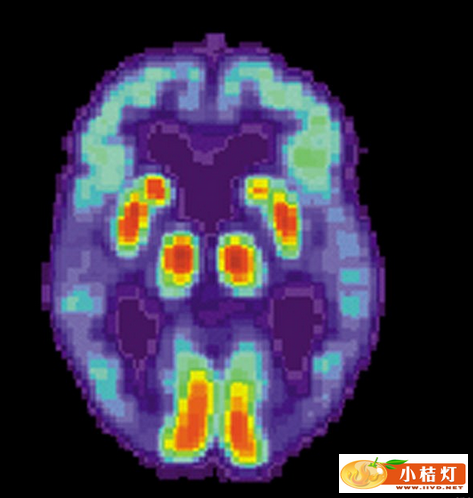

阿尔茨海默症患者大脑的PET扫描图

针对40位试验对象的初步研究数据显示,视网膜的淀粉样蛋白水平与正电子发射断层摄影术(PET)扫描显示的大脑淀粉样蛋白含量水平呈现密切相关性,PET是目前所使用的阿尔茨海默症检测方法。

如果证明其准确性,阿尔茨海默症视网膜成像术检测可能会大大改变阿尔茨海默症的诊断方式。“目前临床试验中使用的测试方法是脑部PET扫描和腰椎穿刺术抽取脑脊液以检测淀粉样蛋白和Tau蛋白水平,”神经视觉公司首席执行官史蒂芬·维尔多纳(Steven Verdooner)说,“我们的视网膜成像术检测的费用有望大大低于PET扫描,它不仅没有创伤,而且检测敏感性可能更高。”

目前,因为PET扫描具有放射性,医生不会对病人进行重复检查,通常要等待至少18个月才安排下一次PET扫描。据维尔多纳说,神经视觉公司的测试可以以三个月一次的频率重复进行。